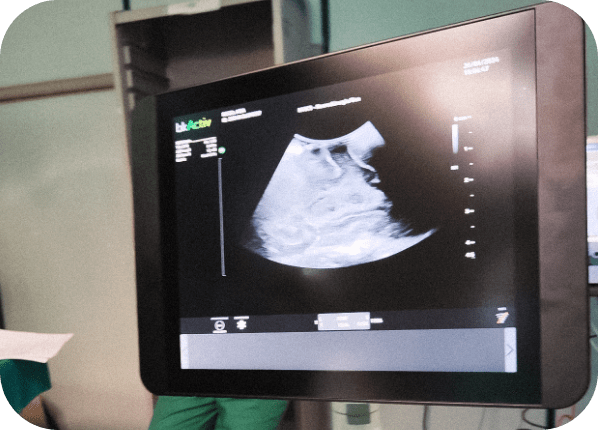

Arrivato in reparto ed in utilizzo da un anno con più di 100 interventi neurochirurgici effettuati. Trattandosi di strumentazione ad alto costo (costo iniziale circa 130 mila euro), l’ecografo è stato acquistato in leasing. Si tratta di un sistema ad alta definizione con il quale è possibile visualizzare e raggiungere con precisione controllata in ogni fase lesioni cerebrali (ad esempio tumori e malformazioni vascolari) sia superficiali, che possono avere un aspetto anche al microscopio operatorio simile alle strutture cerebrali normali, che profonde, consentendone con accuratezza millimetrica la rimozione